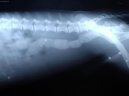

Kočky:  > Cizí tělesa v zažívacím traktu a kostní trus. (Veterinární zákroky) Cizí tělesa v zažívacím traktu a kostní trus. (Veterinární zákroky) - Cizí tělesa jsou jednoduše takové předměty v zažívacím aparátu, které tam zkrátka nepatří.